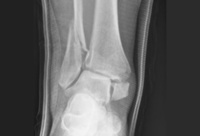

Visão da articulação de encaixe de uma fratura-luxação trimaleolar com ruptura concomitante da sindesmose

Do acervo de B. Petrisor, MD; usado com permissão